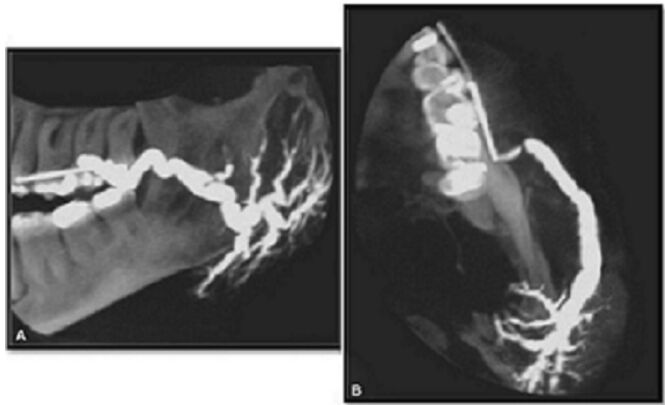

78.附圖兩張X光片所呈現的影像,其臨床診斷最可能是下列何者? (A)纖維性發育不良(fibrous dysplasia) (B)淋巴結(lymph node) (C)造釉細胞瘤(ameloblastoma) (D)涎石病(sialolithiasis)